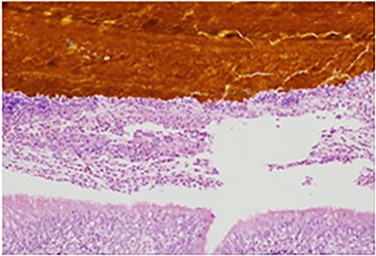

The patient recovered well, but <1 month later he noticed an additional draining sinus at the right flank. A fistulogram (Fig. 1) was performed, and it showed a connection between the sinus and a right lower lobe bronchiole. He was taken to the OR for a right thoracotomy with wedge resection of the right lower lobe of the lung and excision of a broncho-pleuro-cutaneous fistula that was found to contain pieces of golden pigmented solid material, which was concluded to be consistent with a gallstone (Fig. 2). This case report presents a patient with an uncommon complication from a dropped gallstone: a broncho-pleuro-cutaneous fistula.

Specimen histology demonstrating bilirubin deposits within the lung parenchyma